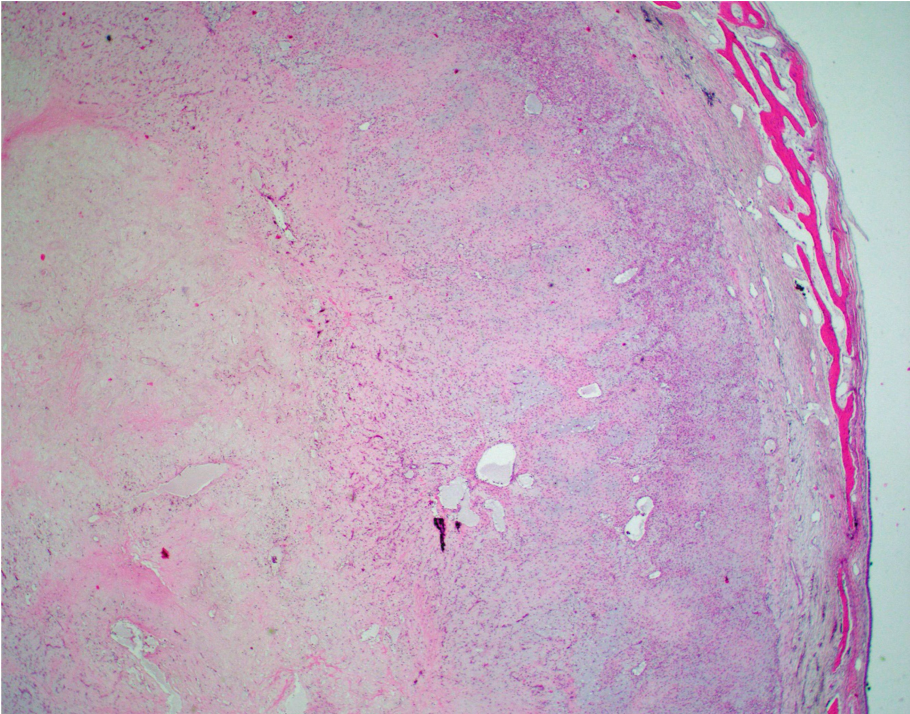

Answer: B.) Chondromyxoid fibroma

Chondromyxoid fibroma (CMF) is a benign neoplasm sharply demarcated from the surrounding bone exhibiting a zonal/lobular architecture. The peripheries of the lobule are more hypercellular and exhibit stellate and spindle-shaped cells and occasional osteoclast-like giant cells. The centers of the lobule are more hypocellular and myxoid with embedded bland stellate and spindle-shaped cells. While the centers of the lobule resemble hyaline cartilage, true hyaline cartilage is rare in CMF.